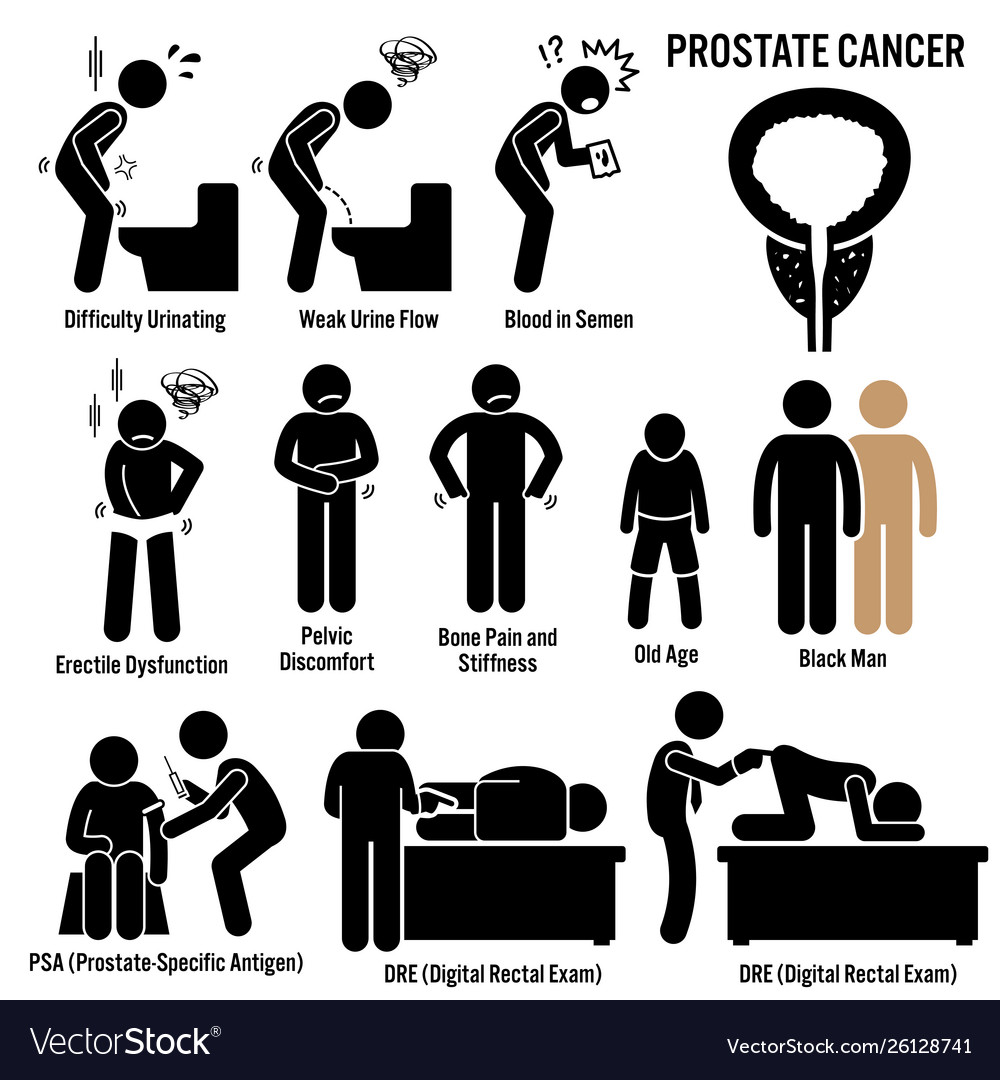

Prostate cancer symptoms causes risk factors Vector Image

Symptoms of Prostate Cancer, Risk Factors and Causes – My Health Only

Early Warning Signs of Prostate Cancer – Hello Doctor

What are the most common earliest symptoms of prostate cancer? – Quora

Prostate cancer is now the most common form of disease in UK – the 7 …